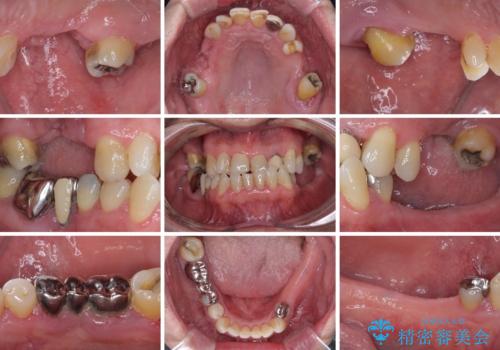

欠損の多い奥歯 インプラントによる補綴治療

- 地元ではなかなかインプラント治療を行ってくださる医院がないとのことで、転勤で東京にいる期間に治療を行いたいとのことで来院された患者様です。

上顎は左右ともに骨が少ない状態であり、特殊なドリルを用いた歯槽骨の拡大や自家骨挙上などを行いながらインプラントを埋入していくこととしました。

右下の銀歯も気になるとのことで、インプラント治療と並行してオールセラミックによるブリッジ補綴治療も行うこととしました。